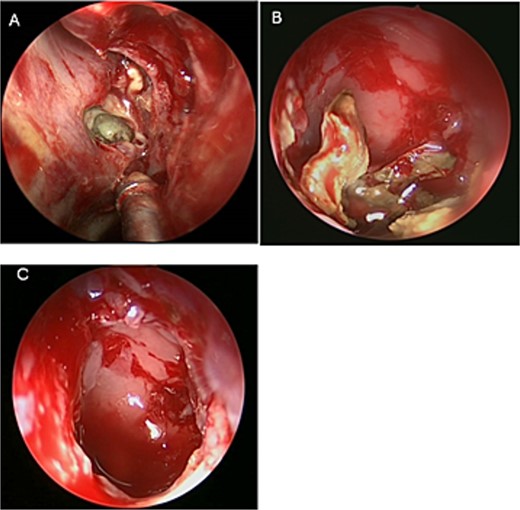

An asthmatic 42-years-old patient who was previously medically treated for allergic rhinitis with no significant improvement. A subsequent CT scan revealed isolated sphenoid sinus disease (Fig. 3). Intra-operative endoscopic findings revealed fungal mud and mucin (Fig. 4A and B) with post-operative (Fig. 4C) endoscopic finding of widely open, clean sphenoid sinus. Further histological examination of the specimen proved the diagnosis of eosinophilic AFS.

Coronal CT scan image showing complete sphenoid sinus heterogenous opacification.